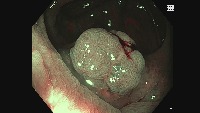

Disease Diagnosis: The "Manifold learning" model can be applied in the medical field to facilitate early detection and diagnosis of oral diseases. By identifying and distinguishing between Adenoma, Hyperplasic, and Adenocarcinoma, this model can assist doctors in understanding a patient's condition and deciding the appropriate treatment method.

Medical Education: The model can be used as a learning tool in medical schools and universities for studying oral diseases. It can aid students in understanding and distinguishing the different classes of oral conditions, providing them with practical insights that textbooks might not offer.

Dental Consultation: Dentists can incorporate this model into their practice to identify and prevent potential oral diseases at a very early stage. This can improve the patient's oral health and could even prevent life-threatening situations with early detection of Adenocarcinoma.

Pharmaceutical Research: Pharmaceutical companies can use this model to analyze the effects of their drugs under development. By observing changes in the mouth before and after treatment, they can track the drug's efficacy in treating these oral conditions.

Telemedicine Applications: The model could be used in telehealth applications to enable remote oral health assessments. This can facilitate patients to get diagnostic reports from the comfort of their homes without physical visits to the hospital or clinic.